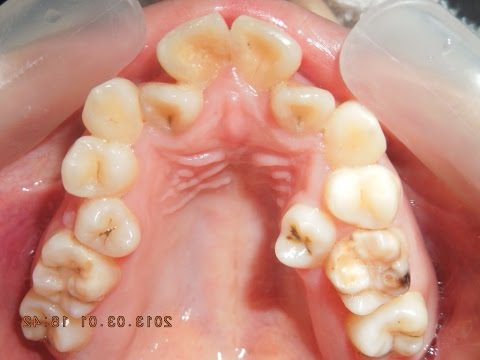

いくら美人でも、口の中は見せられない!!でこぼこフルパワー抜歯矯正 by福岡天神矯正歯科ティース

この口の中をみたら、美人を想像できない。

隠れたところに気を使おう。